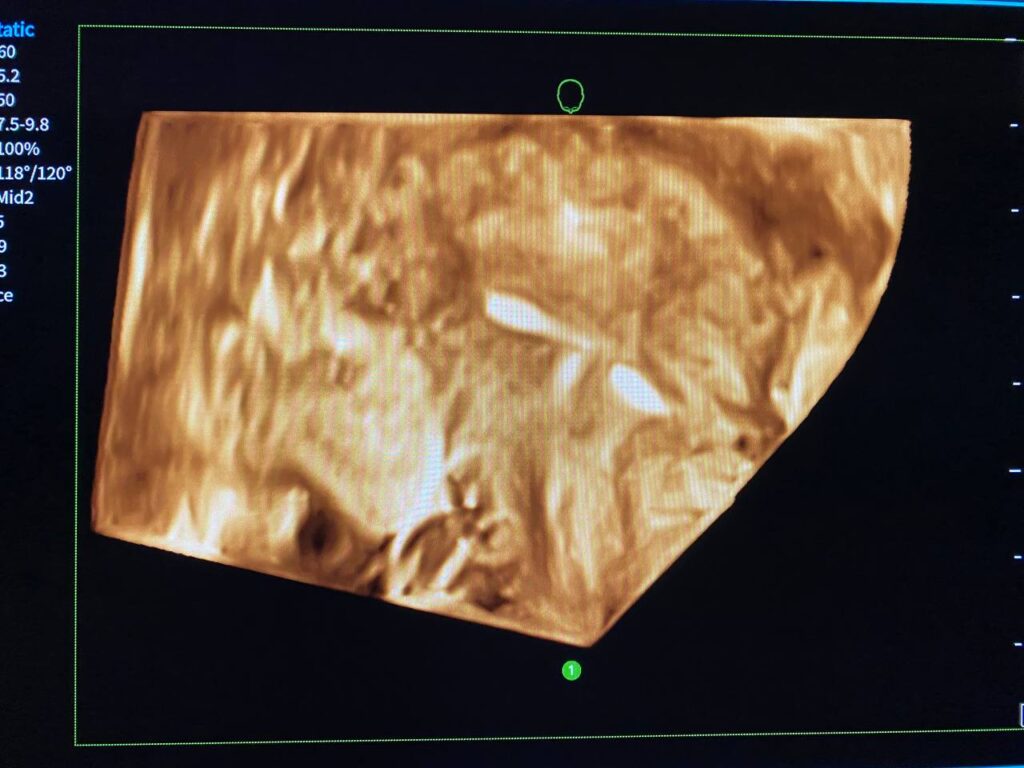

Normal size uterus, endometrial lining thickness 4mm, with IUD about 12mm lower than normal site & left transverse limb piercing the adjacent myometrial layer, clear endo-myometrial junctional zone, no fibroid